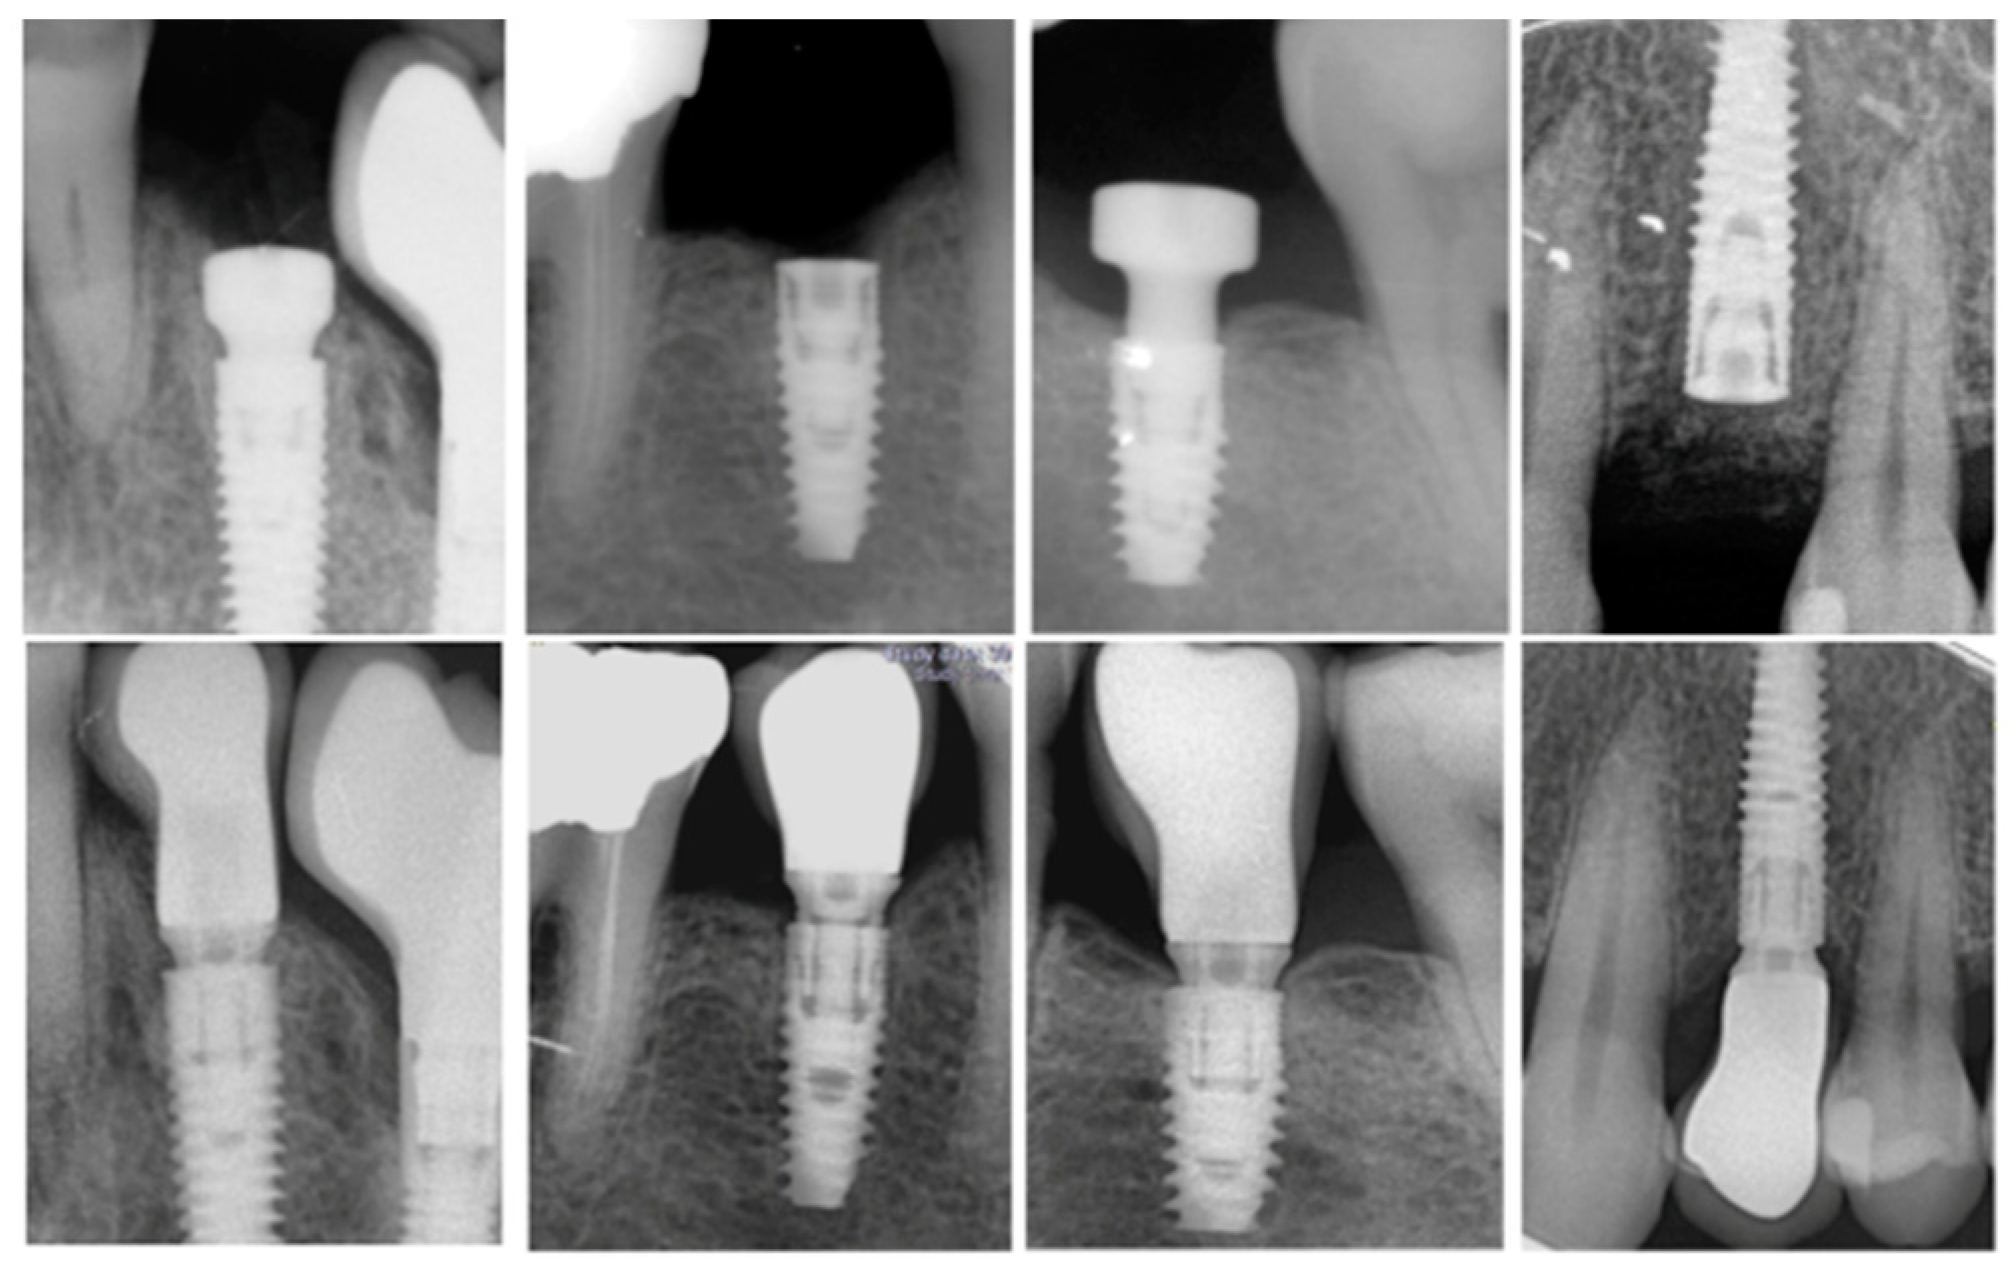

- Depth of implant placement: On the day of the surgery, a periapical radiograph was performed to provide the depth of implant placement read on the proximal sides.